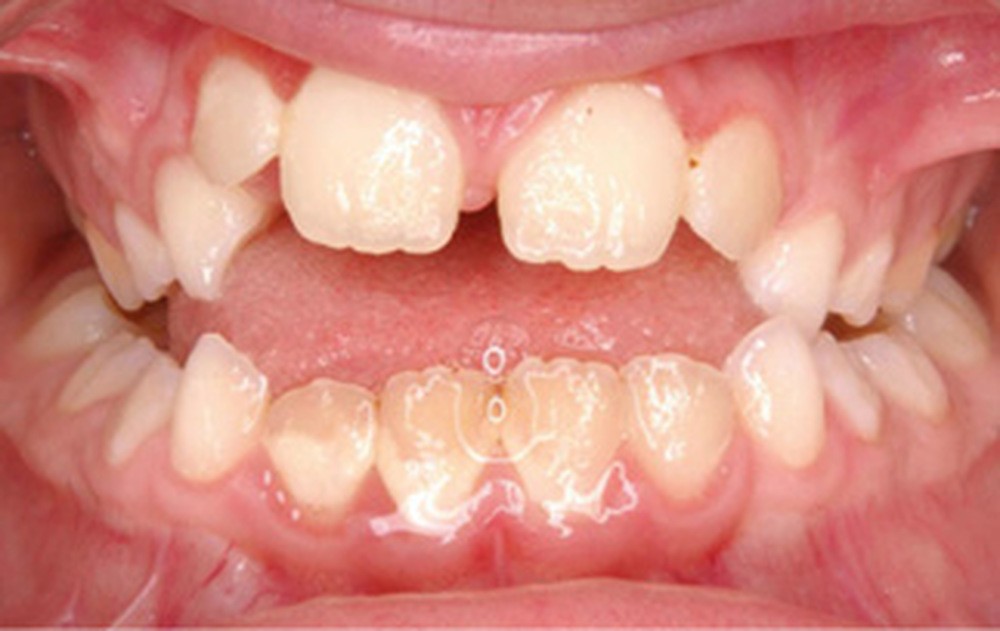

Cette patiente a été suivie dans le cadre d’un traitement interceptif alors qu’elle avait 9 ans. Elle présentait une endognathie maxillaire et une béance antérieure importante liées à des troubles fonctionnels évidents. En effet, l’examen clinique révélait une ventilation buccale exclusive, des ronflements nocturnes et une déglutition atypique. Nous avions noté à l’époque un manque de place pour l’évolution des dents définitives et un inversé d’articulé bilatéral. Les parents avaient rencontré un médecin ORL, mais avaient refusé une intervention visant à enlever les amygdales. Les deux canines maxillaires étaient incluses (fig. 1 à 6).

Quelques années plus tard, au moment de démarrer sa prise en charge orthodontique, la patiente présentait à nouveau une béance antérieure, un décalage des milieux incisifs de 2 mm et le problème transversal avait récidivé. Lors de l’examen clinique, elle présentait un inversé d’occlusion bilatéral postérieur et une ventilation buccale exclusive. À la suite du refus de réaliser l’amygdalectomie de façon précoce, elle ronflait toujours et sa déglutition ne s’était pas modifiée malgré des séances d’orthophonie (fig. 7 à 15).